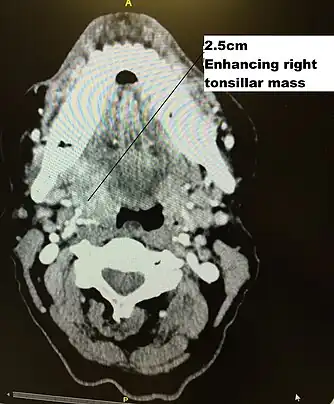

CT scan in transverse plane, viewed from below, showing a contrast enhancing right tonsil mass due to HPV+OPC